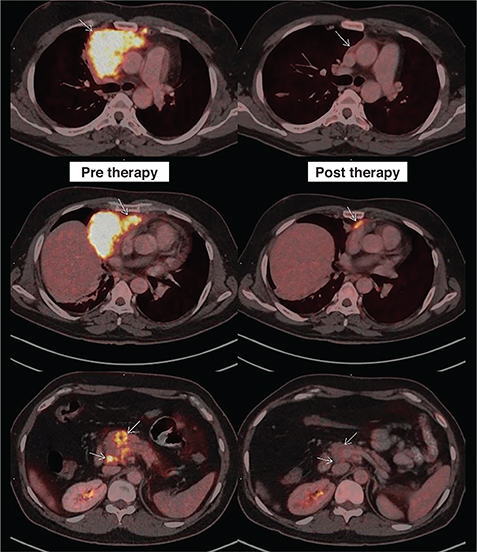

The results of 18F-FDG PET/CT, which are used during and after treatment for HL and aggressive NHL, have a high prognostic value and correlate with survival. Updated response criteria for aggressive lymphomas now include 18F-FDG PET/CT. Figure 5 shows the impact of the interim response assessment with 18F-FDG PET/CT by demonstrating the minimal persistent residual metabolically active disease (with Deauville score 4) which would have been interpreted by conventional anatomic imaging modalities as post-treatment fibrotic residue.

Fig 5

Figure 5. Staging and interim response assessment 18F-FDG PET/CT scans. 18F-FDG PET/CT images include fused axial PET/CT of the patient taken during staging on the left column and interim response assessment after 3 cycles of chemotherapy on the right column (comparative lesions marked with small white arrows). First row showing complete resolution of the bulky component of the disease. Second row showing persistent minimal metabolically active residual disease (Deauville’s score 4) abutting the pericardium and third row showing complete resolution of the pancreatic lesion and adjoining peripancreatic lymph node.